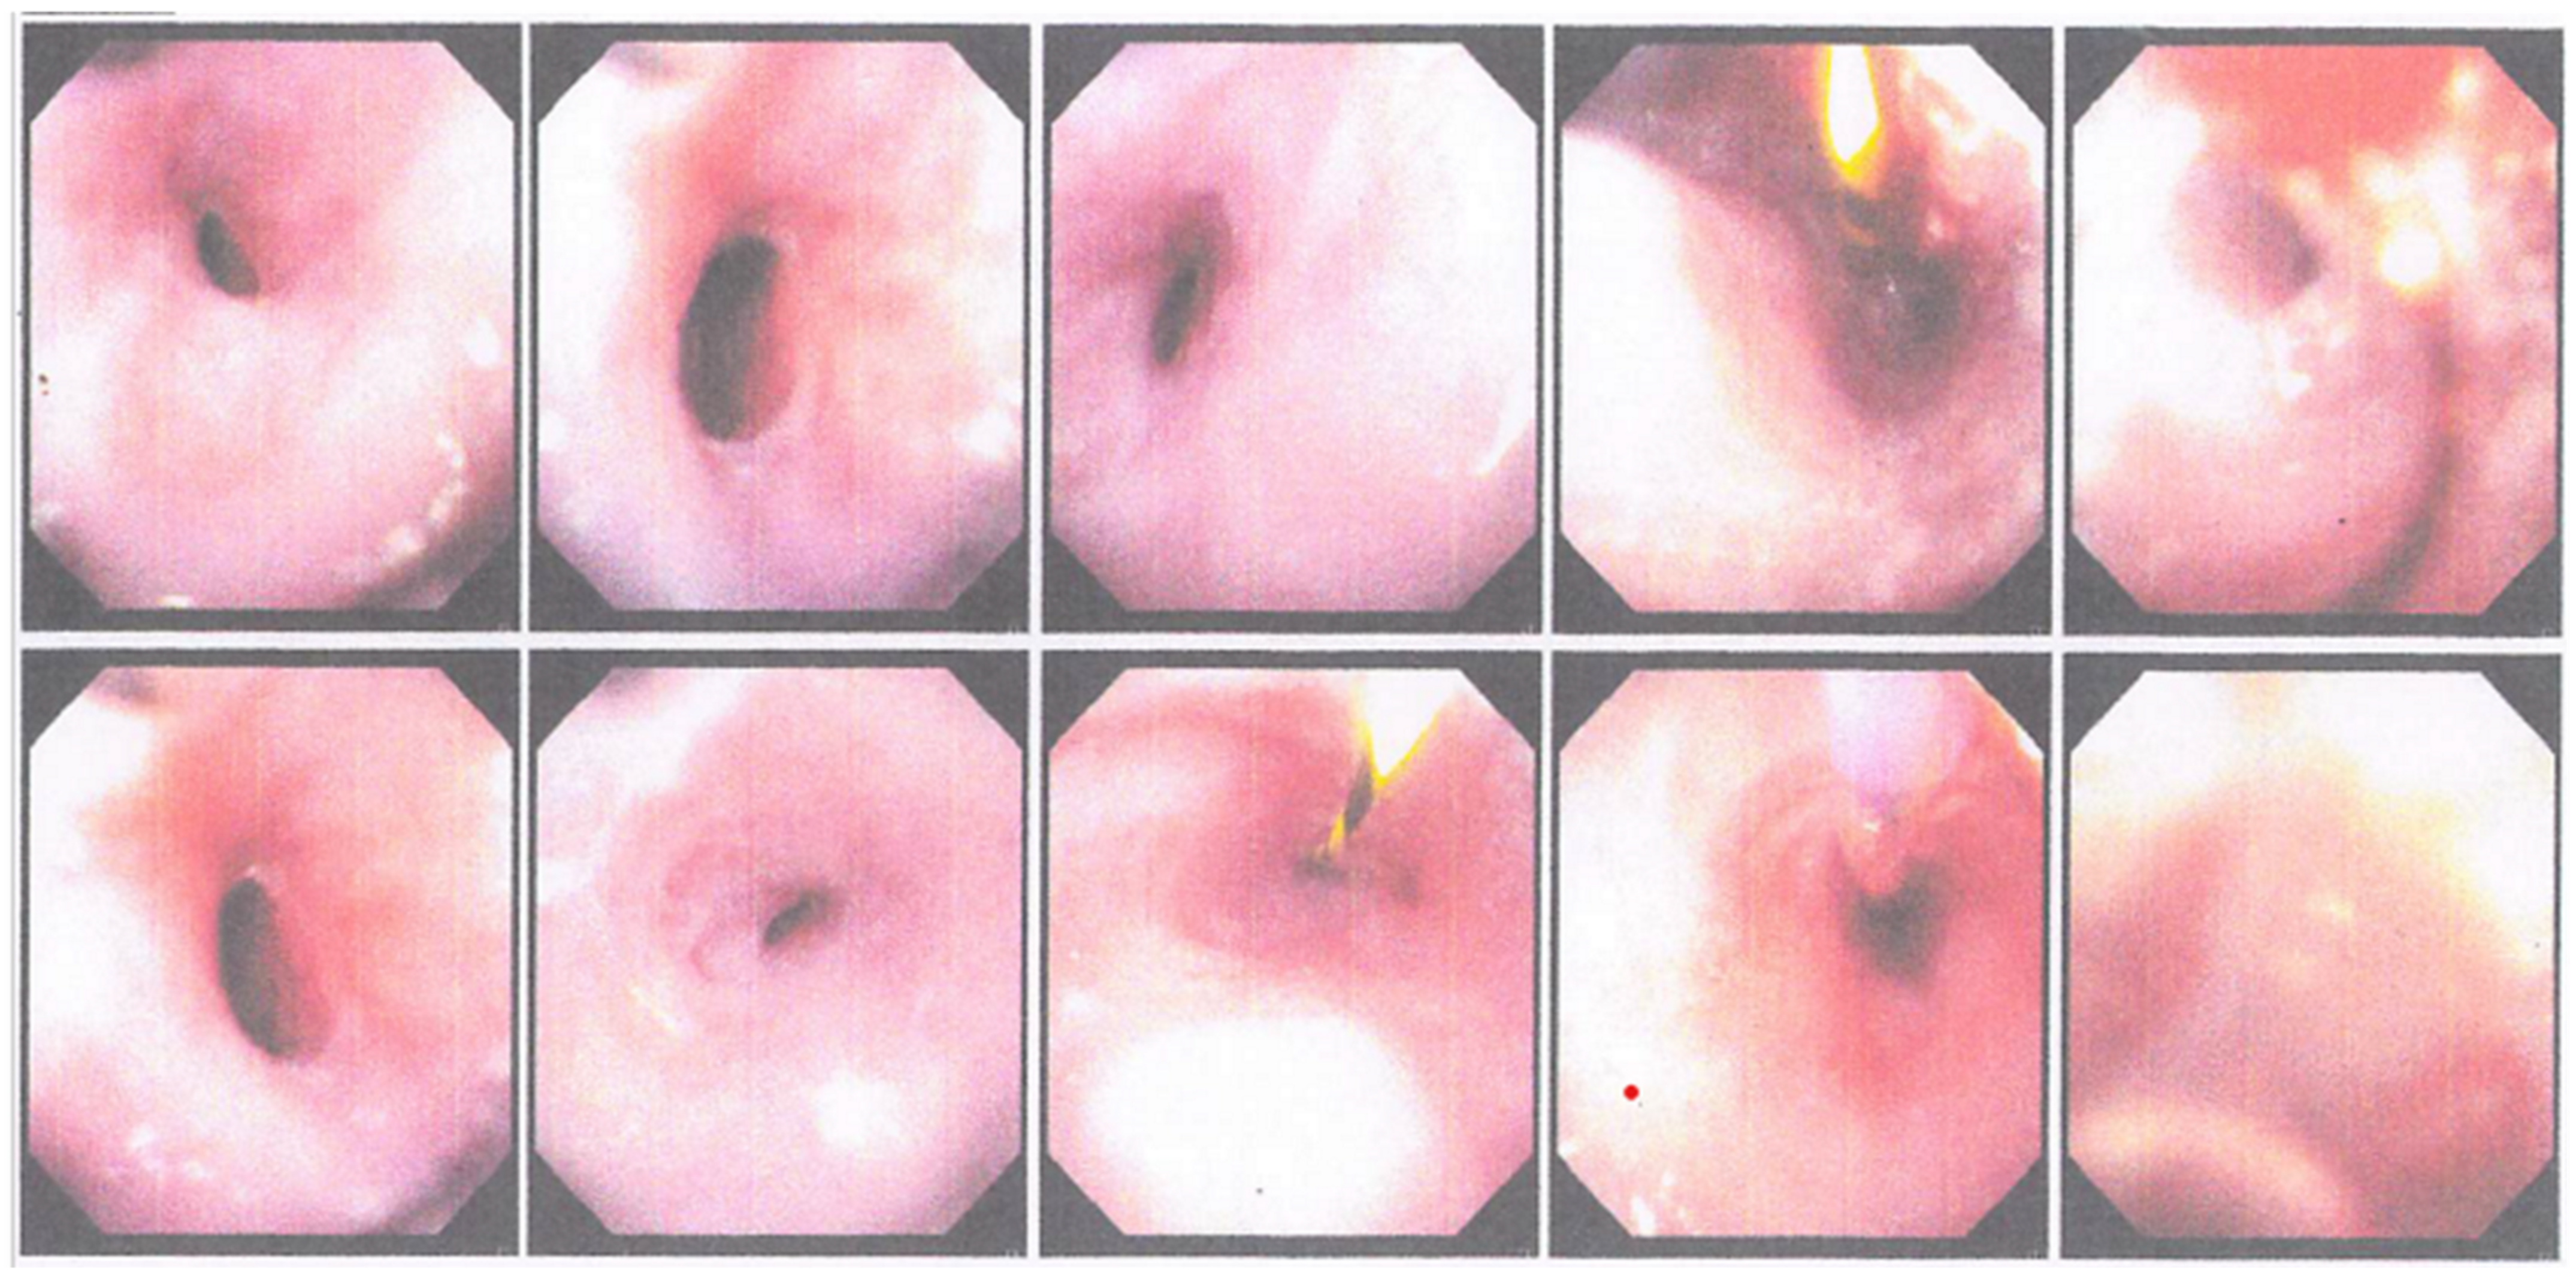

Two weeks after the second EGD, the patient returned for the third EGD (Figure 5) and obtained the following results: the scope could go through the oral cavity up to D2. In the esophagus, there was a narrowing of the esophageal lumen starting 25–30 cm from the incisors. Dilation was carried out using 1ATM/2ATM/3ATM CRE balloons for 1 min each. Post dilation, mucosal break was visible, and no active bleeding was seen. There were two polyps in the distal esophagus. On the gastric cardia, a mass resembling granulation tissue was seen (the red dot in Figure 5), and a biopsy was performed. The fundus and body of the stomach showed no abnormalities. In the gastric antrum, an ulcer was seen with granulation tissue and cicatricial tissue, and a biopsy was performed. Normal pyloric ostium was observed. In the duodenum, the D1 and D2 villi were intact. Based on these findings, it was concluded that there was an esophageal stricture due to corrosive injury that had been dilated, as well as esophageal polyps, masses (granulation impressions) on the cardia and ulcers on the gastric antrum. Proton pump inhibitors and mucoprotectors were advised, as well as a high-protein coarse porridge diet and the patient was scheduled for another round of esophageal dilation within 2 weeks after the third EGD.

Figure 5. The third round of EGD performed at the Dr. Soetomo General Academic hospital.